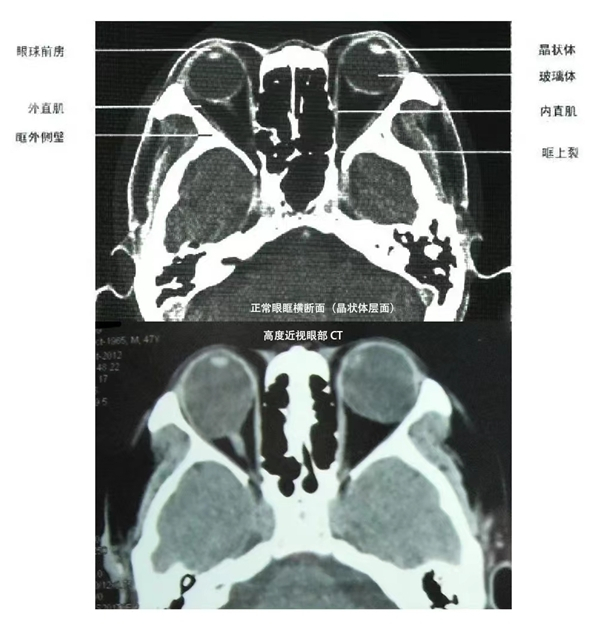

先别着急,一起看看下面的对比图吧

四、眼球容量变大,正常人的眼球容量只有4.5ml,组织结构包括视网膜、脉络膜和巩膜三层,三层之间都是紧密贴附的。1000度以上近视患者眼球容量甚至可以达到正常人眼球容量的一倍以上,眼球的容量就好比气球,如果眼球变大到了本身体积的一倍以上,相应的视网膜厚度就会变薄,同时眼球变大会导致视网膜、脉络膜和巩膜之间的附着出现撕裂,从而导致视网膜变性、黄斑劈裂、甚至视网膜脱离。